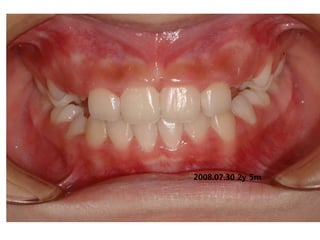

1999.05.26 /M

C.C

• Crooked teeth

Dx

• Lack of space caused by perioral muscle action

Goal

• Establish normal tongue posture and lip tone

with T4K

2008.07.30.2y